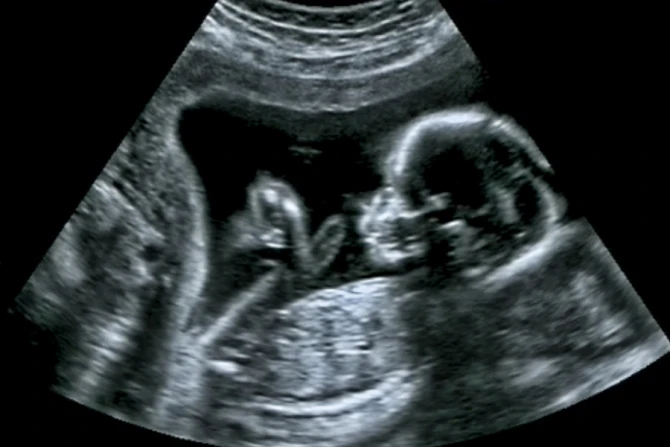

She told her doctors that she held religious beliefs contrary to those of the booklet. She claimed her religious beliefs meant they did not need to follow the informed consent requirements. Planned Parenthood declined to ignore the law's provisions, which include a mandatory 72-hour waiting period and offering an ultrasound.